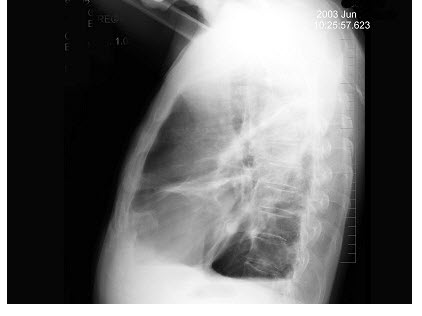

男,24岁,低热、乏力数周,夜间偶有盗汗,胸片如图,最可能的诊断是()

A.细支气管肺泡癌

B.肺转移瘤

C.两肺炎症

D.血型播散型肺结核

E.结节病

点击查看答案